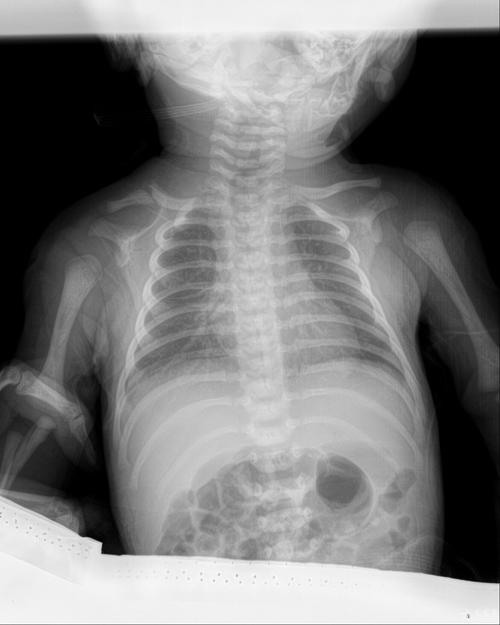

- 检查肺部:判断是否有新生儿肺炎、肺不张、吸入综合征等。

- 检查骨骼:查看是否有骨折(尤其是难产或产伤的新生儿)、骨骼发育问题。

- 检查腹部:观察是否有肠梗阻、坏死性小肠结肠炎等消化道疾病。

- 检查胸部心脏:观察心脏大小、形态,初步筛查先天性心脏病。